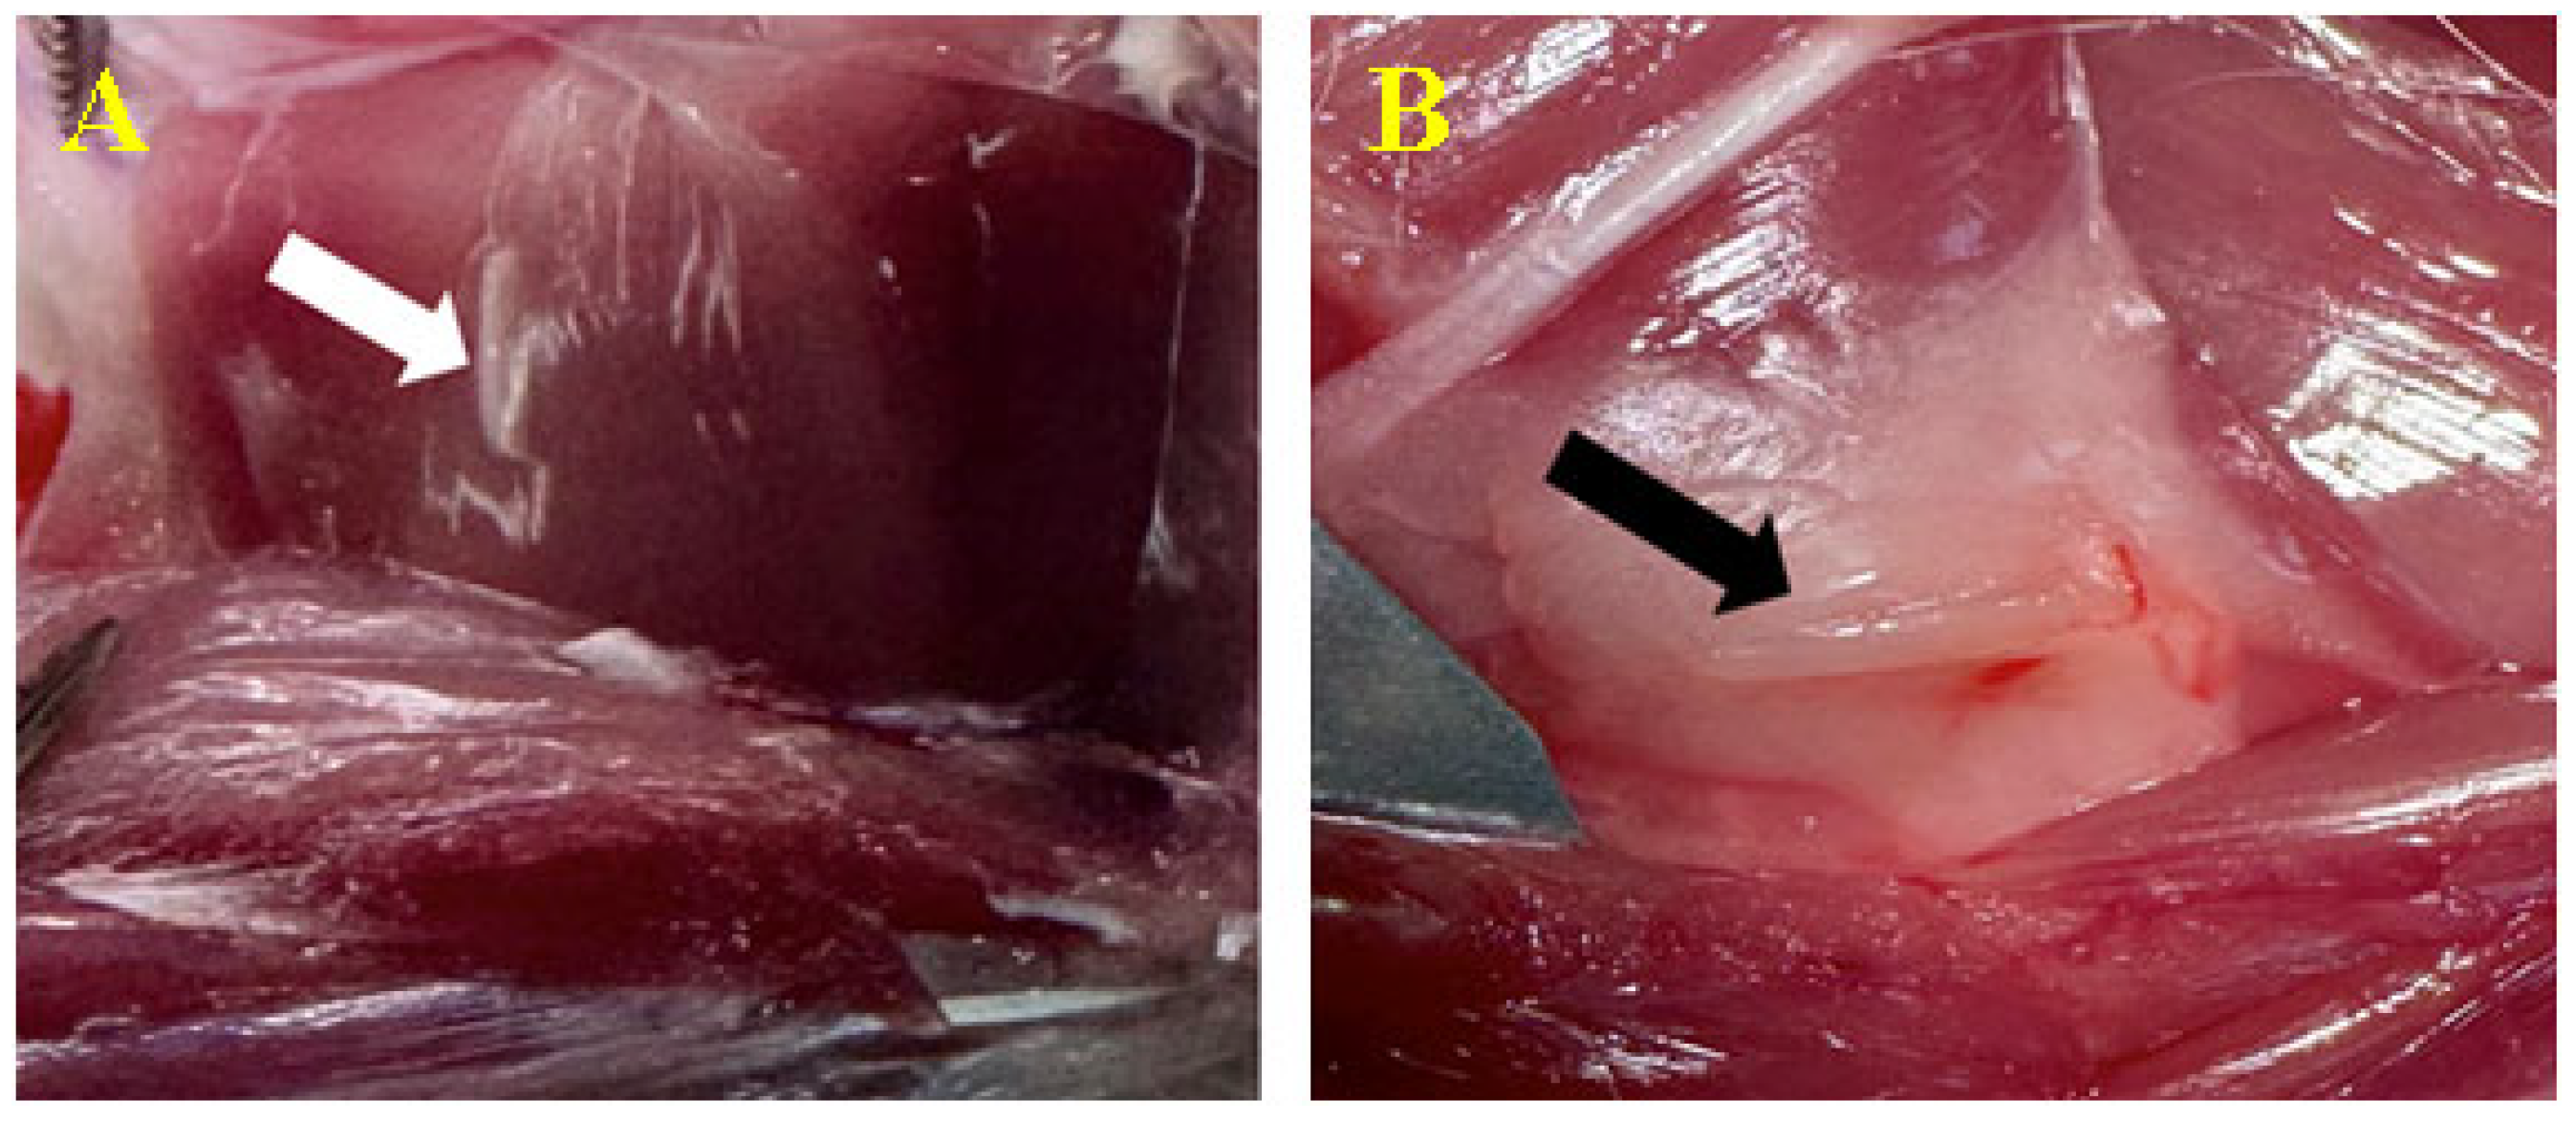

2.6.2. Intramuscular/Perimuscular

3.3.2. Peri/Intramuscular